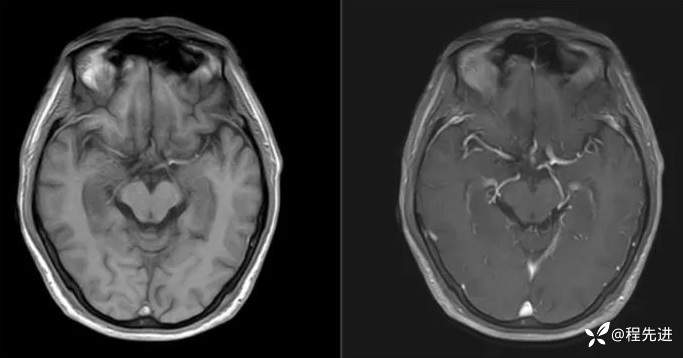

T1、T1增强: